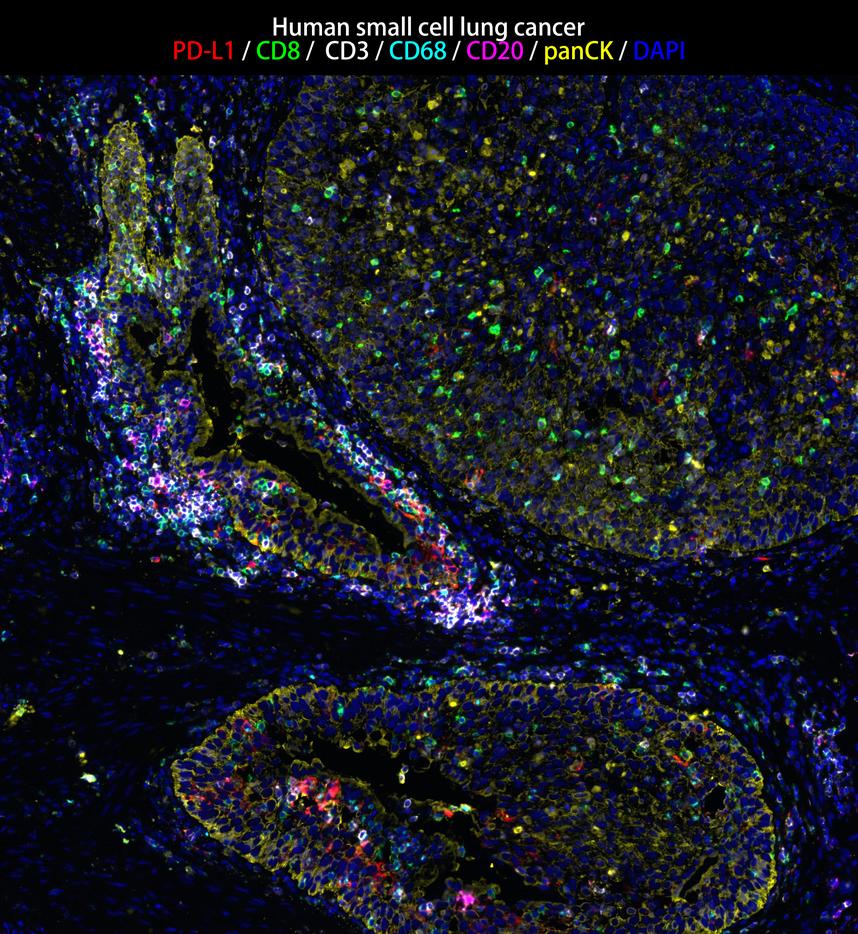

IRS003_6.jpg Fig6: mIHC analysis of human small cell lung cancer tissue (Formalin/PFA-fixed paraffin-embedded sections) with PD-L1, CD8, CD3, CD68 (IRS004), CD20 (IRS003) and panCK (IRS010) antibody at 1/100 dilution. The immunostaining was performed with the IRISKitCmTSA Kit (900802). Heat mediated antigen retrieval with Tris-EDTA buffer (pH 9.0) for 30 mins at 95℃. DAPI (blue) was used as a nuclear counter stain. Image acquisition was performed with Olympus VS200 Slide Scanner.